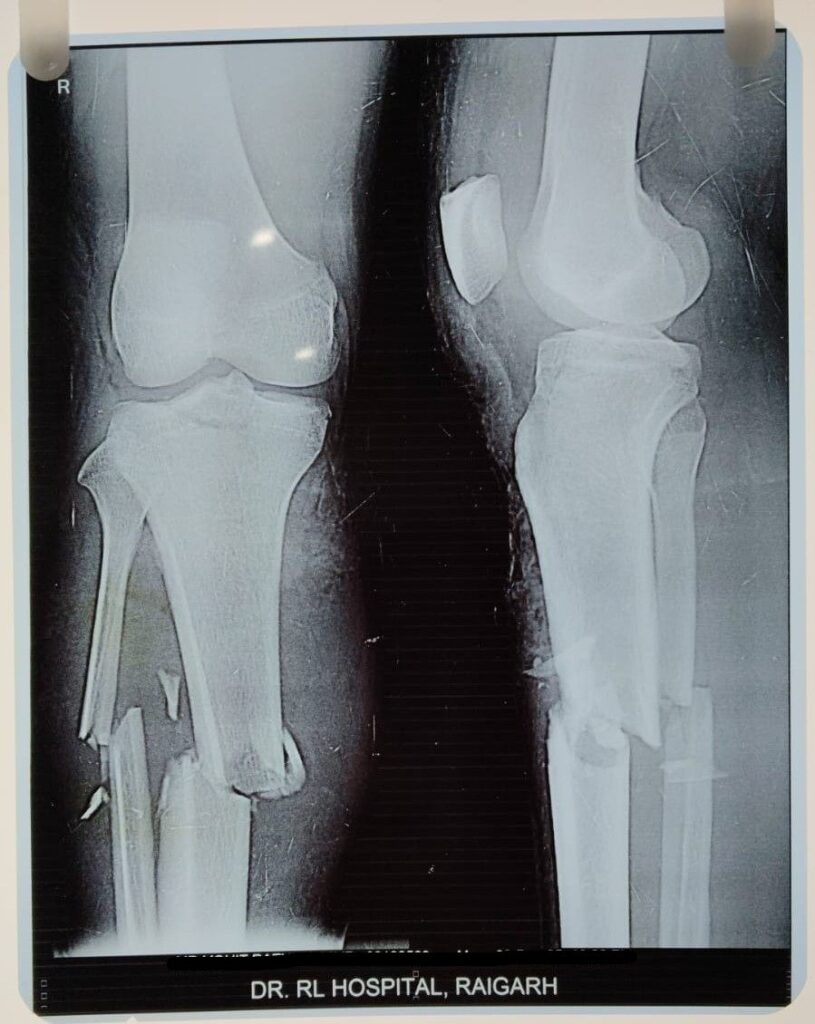

क्या कहते है डॉक्टर…. इस सम्बन्ध में डॉ.आर.एल.हॉस्पिटल के हड्डी रोग विशेषज्ञ डॉ. प्रशांत अग्रवाल ने बताया कि 25 वर्षीय पुरुष नाम न छापने के शर्त पर जो रायगढ़ निवासी है अपने गाँव से बाइक मे जा रहा था सामने से आ रही अन्य बाइक से टकरा जाने से गंभीर रूप से चोटग्रस्त हो गया था, अस्पताल जाँच हेतु आया था। टक्कर की वजह से मरीज का ( डिस्टल रेडियस फ्रैक्चर) हड्डी के कलाई के पास वाला सिरा जो कलाई को गति प्रदान करता है टूट गया था। इसके अलावा (टीबीया फिबुला ) पिंडली की बड़ी हड्डी व पिंडली की छोटी हड्डी जो टीबीया के साथ मिलकर निचले पैर का निर्माण करते है जिसमे टीबीया मुख्य भाग उठाने वाली हड्डी होती है l व फिबुला सहारा देती है दोनों टूट गया था व ( पी. सी. एल.) धागा जो घुटने के पीछे का मजबूत लिगामेन्ट होता है। जो जाँघ की हड्डी (फिमर ) को पिंडली की हड्डी (टीबीया ) से जोड़ता है वह भी टूट गया था मरीज असहनीय दर्द से कराह रहा था। डॉक्टर ने मरीज तात्कालिक जाँच कर भर्ती कराने की सलाह दी। इस तरह के जटिल व मल्टीपल चोट बिना ऑपरेशन के ठीक नई हो पता है। हॉस्पिटल के डायरेक्टर व हड्डी रोग विशेषज्ञ डॉ. प्रशांत ने मरीज के परिजन को सारे शल्य क्रिया के बारे मे बताया व ऑपरेशन हेतु प्रेरित किया। व अस्पताल मे कार्यरत हड्डी रोग विशेषज्ञ डॉ अनंत सिंग के साथ मिलकर मरीज को तीन चरणों मे ऑपरेशन उसे नया जीवन दिया l डॉ. आर. हॉस्पिटल की टीम ने यह मल्टीपल सर्जरी करके मरीज को एक बड़े परेशानी से बाहर निकाला। मरीज अब पूरी तरह स्वस्थ है व चल फिर सकता है।